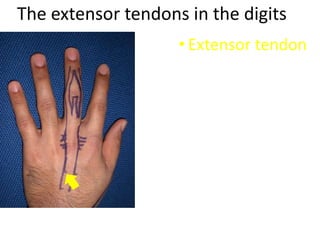

- It describes flexor tendon zones, extensor compartments, and pulley system anatomy.